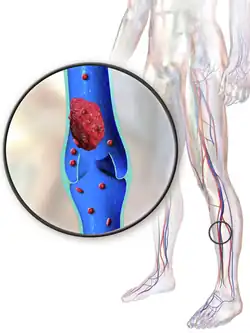

Deep vein thrombosis

Deep vein thrombosis (DVT) is a type of venous thrombosis involving the formation of a blood clot in a deep vein, most commonly in the legs or pelvis.[9][a] A minority of DVTs occur in the arms.[11] Symptoms can include pain, swelling, redness, and enlarged veins in the affected area, but some DVTs have no symptoms.[1]